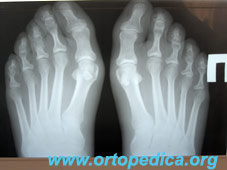

Лечение деформации пальцев стоп (Галлюкс Вальгус)

Рентгенограммы стоп до операции